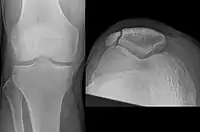

Transverse fracture of patella

Comminuted fracture of patella

Osteochondral fracture of patella

Vertical patella fracture